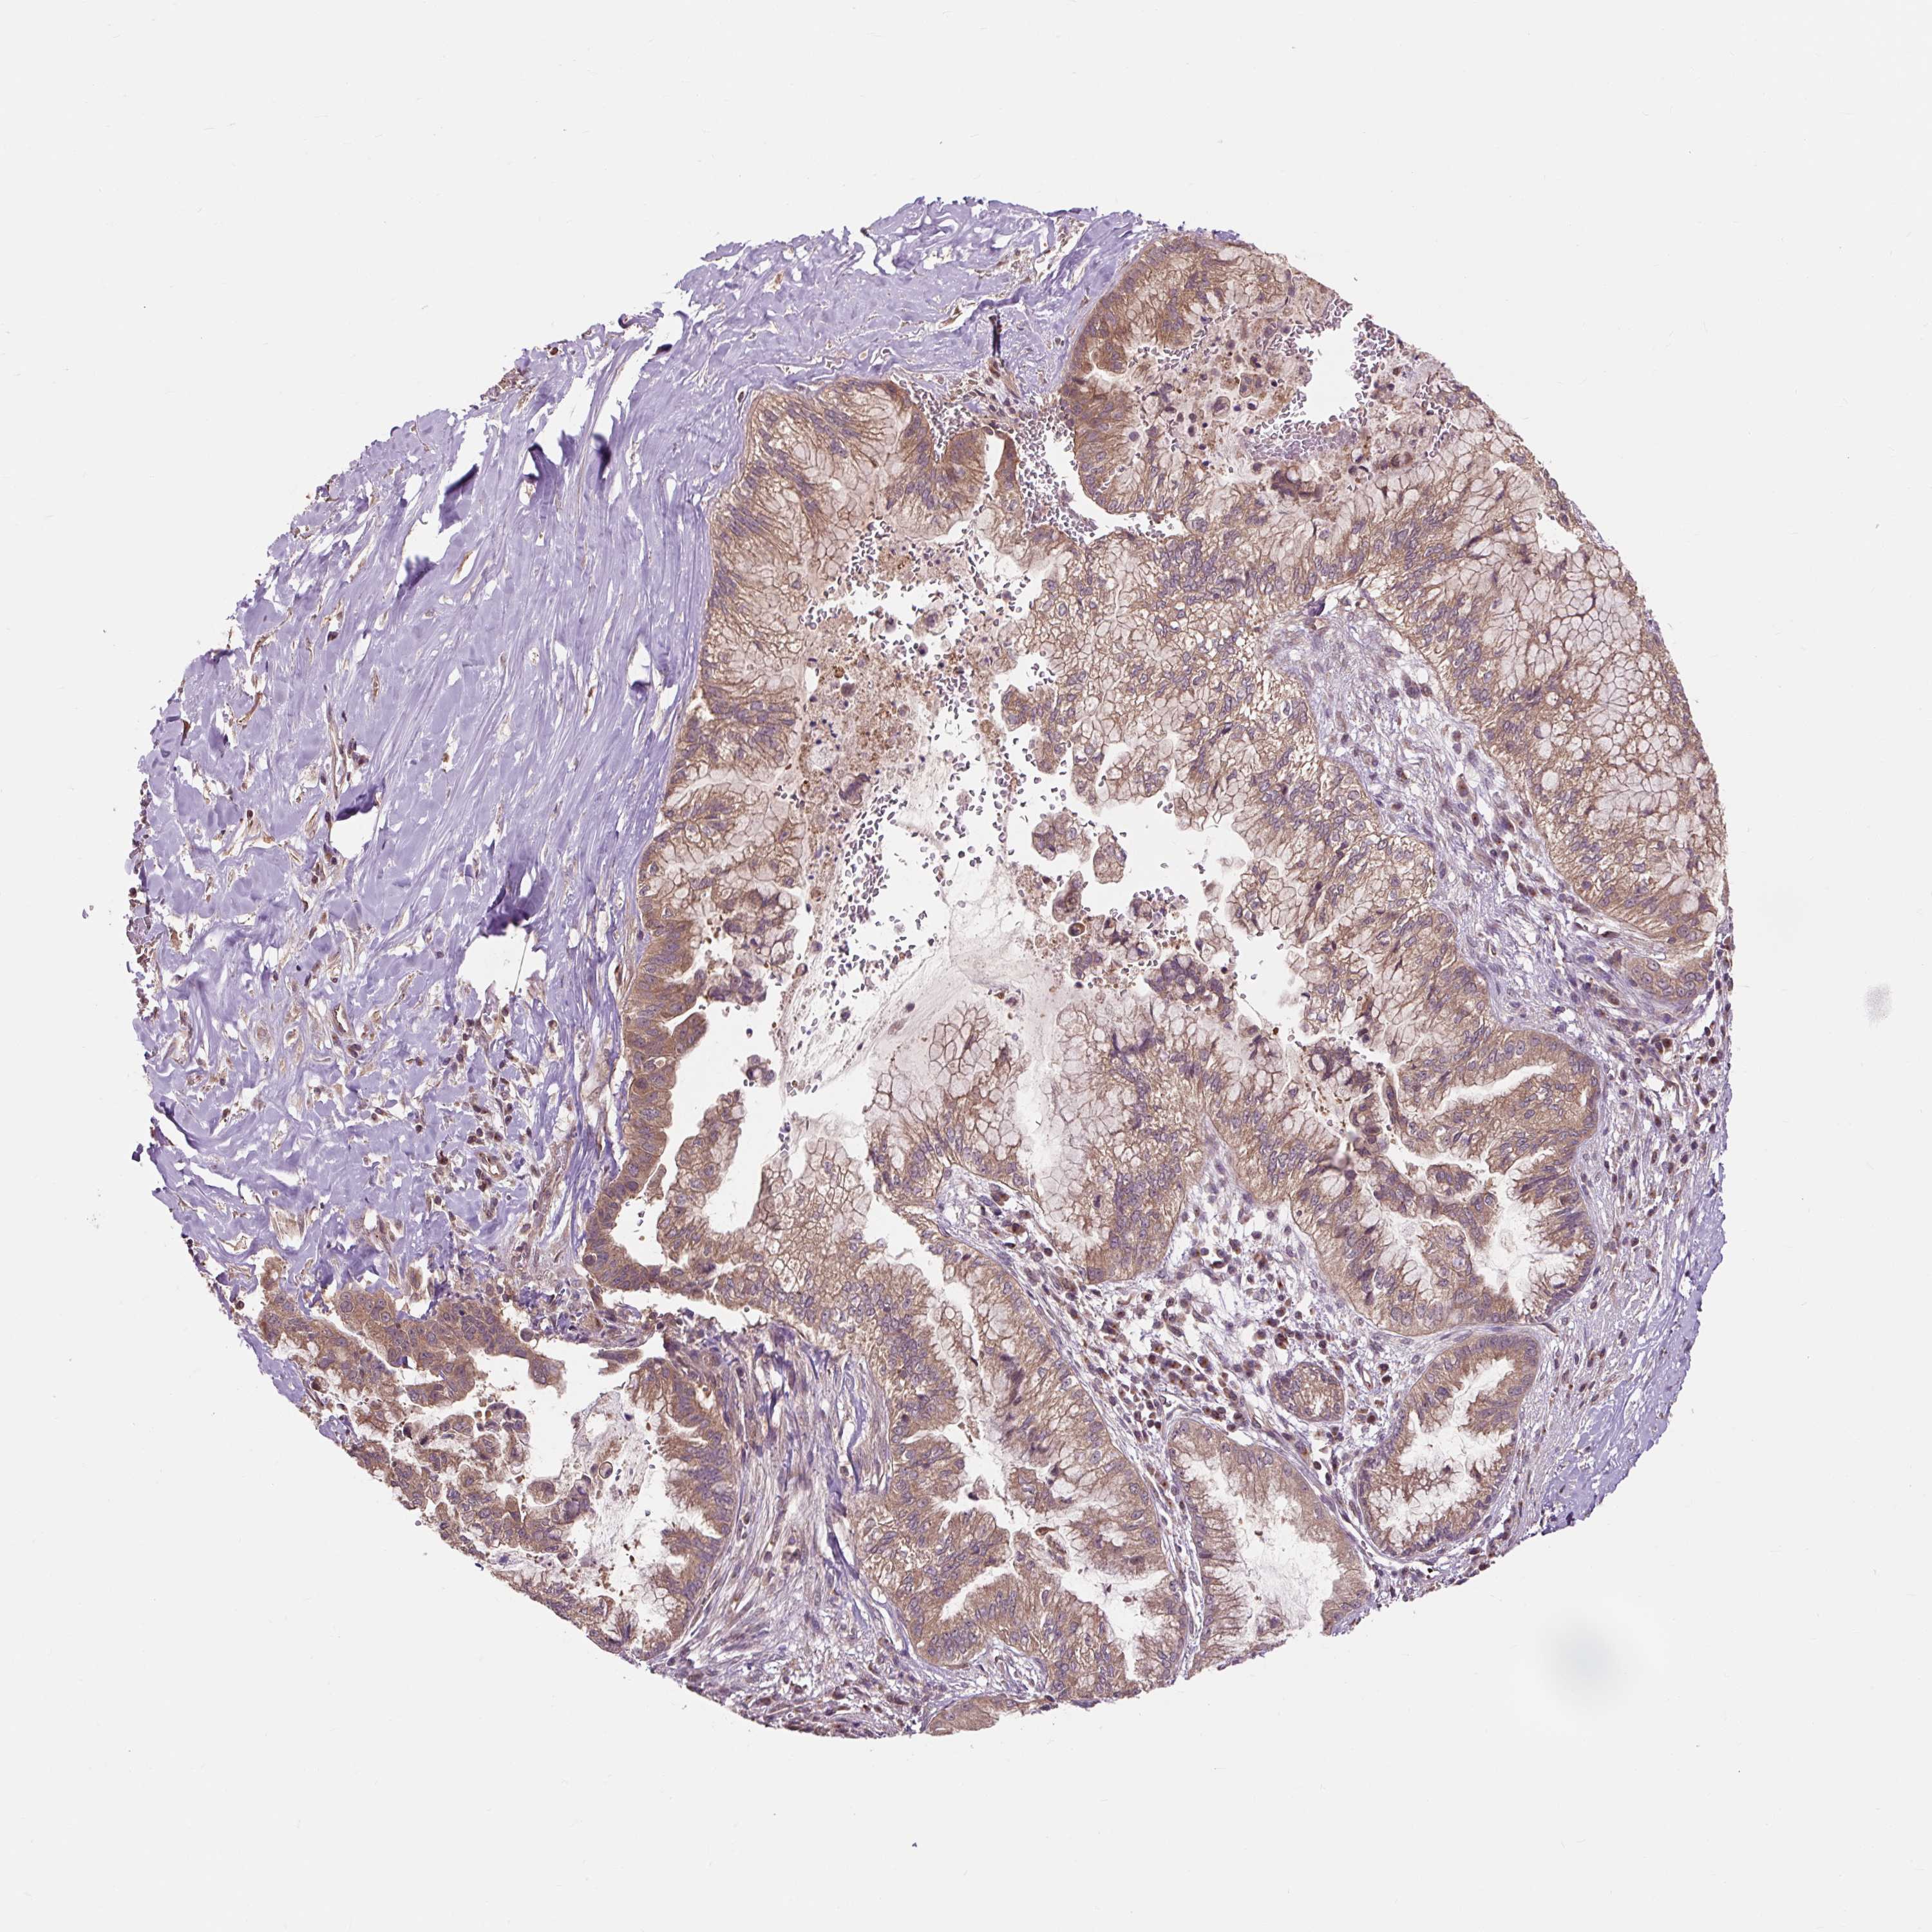

PANCREATIC CANCER - Protein expressioni

A mouse-over function shows sample information and annotation data. Click on an image to view it in a full screen mode. Samples can be filtered based on level of antibody staining by selecting one or several of the following categories: high, medium, low and not detected. The assay and annotation is described here.

Note that samples used for immunohistochemistry by the Human Protein Atlas do not correspond to samples in the TCGA dataset.

Antibody stainingi

Antibody staining in the annotated cell types in the current human tissue is reported as not detected, low, medium, or high, based on conventional immunohistochemistry profiling in selected tissues. This score is based on the combination of the staining intensity and fraction of stained cells.

Each image is clickable and will lead to virtual microscopy that enables deeper exploration of all samples and also displays staining intensity scores, fraction scores and subcellular localization as well as patient and tissue information for each sample.

Antibody HPA056299

Staining

High

Medium

Low

Not detected

Intensity

Strong

Moderate

Weak

Negative

Quantity

>75%

75%-25%

<25%

None

Location

Nuclear

Cytoplasmic/membranous

Cytoplasmic/membranous,nuclear

Adenocarcinoma, NOS